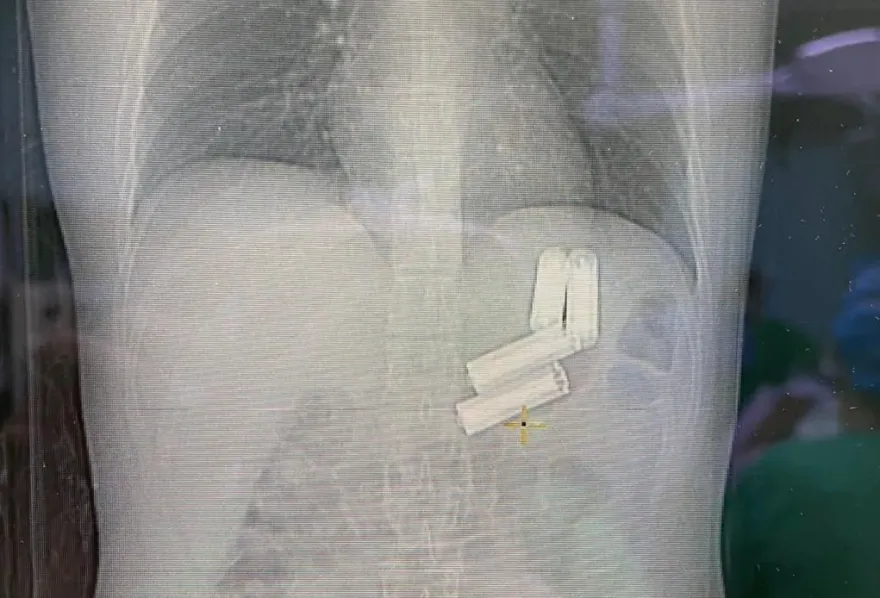

手術

柿石

鞣酸

腸阻塞

異食癖

頭髮

胃石